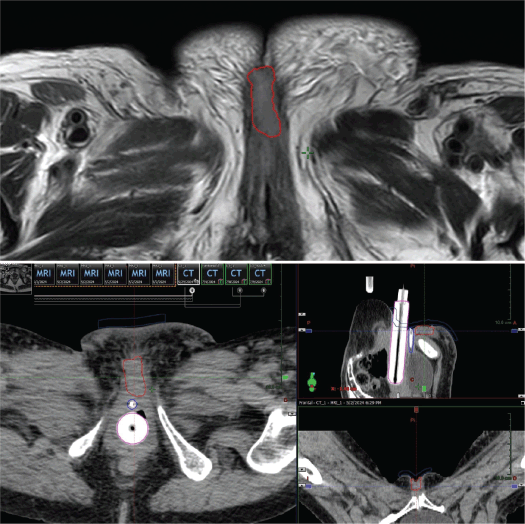

A 75-year-old with a history of hypertension and dilated cardiomyopathy was diagnosed with Stage IIIC2 endometrial adenocarcinoma after hysterectomy, bilateral salpingo-oophorectomy and lymph node dissection revealed one positive para-aortic node. She declined or missed timely adjuvant radiotherapy. Seven months after surgery, the patient presented with a symptomatic recurrence in the vaginal vault and a positron emission tomography - computed tomography (PET-CT) also revealed latero-aortic hypermetabolic adenopathy. She received letrozole for hormone receptor–positive disease and six cycles of palliative chemotherapy with Carboplatin – Paclitaxel, after which she had complete regression of the adenopathy and stability of the disease in the vaginal vault. Then she was treated with palliative EBRT (30 Gy in 10 fractions) to the pelvis and vaginal vault. One year after this treatment, she developed progression of local disease involving the distal vagina and possibly the urethra (Figure 6). The case was discussed in tumour board, and pelvic exenteration was considered but deemed too morbid. She was referred for HDR interstitial BT reirradiation.

Figure 6. Case 2. PET-CT scan prior to BT. Axial, sagittal and coronal section. A hypermetabolic tumour mass in the vaginal vault and a left pelvic lymphocele were observed.